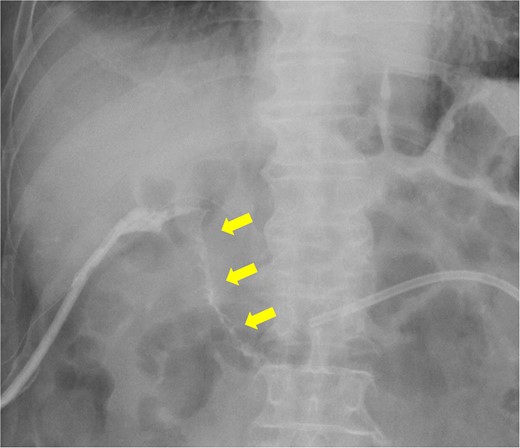

Fistulography reveals recurrence of the duodenal fistula. Fistulography at POD 44 showed recurrence of the duodenal fistula (arrows).